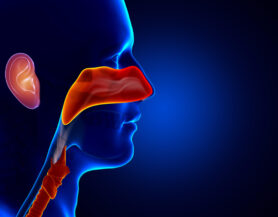

Ear, Nose, and Throat (ENT) Care